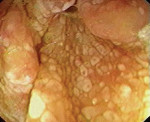

Для диагностики болезни Уиппла используется комплексный подход, включающий клиническое обследование, лабораторные исследования и биопсию пораженных тканей. Важным этапом является обнаружение бактерии Tropheryma whipplei в образцах тканей или жидкостей с помощью полимеразной цепной реакции (ПЦР).

Одним из основных методов диагностики является лабораторное исследование. Для этого пациента просят сдать образцы крови, мочи или стула для анализа. В лаборатории проводятся различные тесты, включая исследование ДНК патогена, что позволяет идентифицировать его присутствие и определить его вид.

Важно отметить, что болезнь Уиппла может имитировать другие заболевания, что усложняет диагностику. Поэтому при подозрении на данное заболевание проводятся дополнительные исследования, такие как гистопатологический анализ образцов тканей или рентгенография суставов. Эти методы позволяют выявить характерные изменения, характерные для болезни Уиппла.